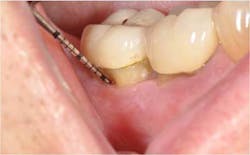

In the present case, a 61-year-old male was referred to my periodontal office by his general dentist for an evaluation of pain and bleeding to the lower right mandible. The patient’s medical history consisted of controlled type 2 (noninsulin dependent) diabetes and hypertension. Upon review of the panoramic radiograph (figure 1), the periodontal defects are not clearly evident, thus showing the importance of proper radiographs to detect periodontal defects. The periapical radiographs (figure 2) clearly show subgingival calculus, grade 1 furcation on No. 30, grade 3 furcation on No. 31, and an advanced intrabony defect on the distal of No. 30. Clinically, there was no mobility to either No. 30 or 31 and both teeth were vital. Tooth vitality is an extremely important diagnostic factor in treatment panning. Periodontal charting of the lower right was also performed, and the lower right exhibited bleeding and inflammation (figure 3).

The patient returned for a postop appointment at 5.5 months and a new radiograph (figure 5) and clinical photographs (figures 6 and 7) were taken. Excellent regeneration is evident at both sites radiographically and clinically. New periodontal charting was done (figure 8) showing near-complete regeneration of the intrabony defect on the distal of No. 30 and a great improvement in the furcation of No. 31. There is no bleeding or inflammation present at this time.